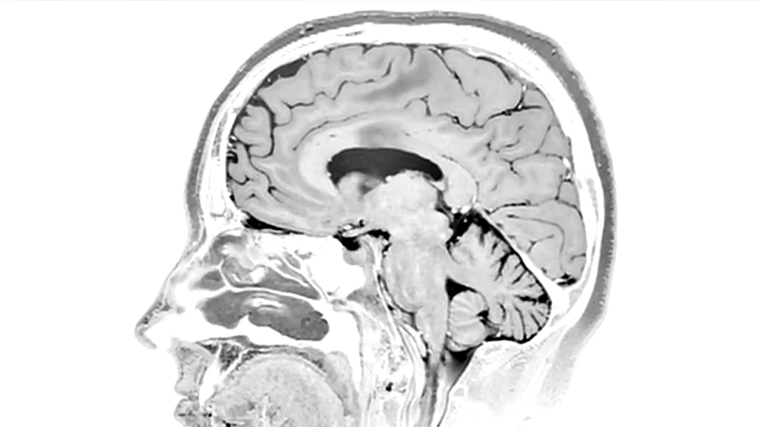

Первичная головная боль подразумевает то, что врачи не видят ее причин на снимках магнитно-резонансной томографии (МРТ) или в анализах.

Как правило, инструментальная диагностика, например, рентген черепа, магнитно-резонансная томография (МРТ) или компьютерная томография (КТ) головного мозга, электроэнцефалография, ультразвуковая допплерография или дуплексное сканирование сосудов головы и шеи неинформативны при мигренях.

Мигрень на самом деле оказывает негативное влияние на мозг. Некоторые пациенты, испугавшись сильных головных болей или связанных с нею предшествующих симптомов ауры, проходят МРТ-диагностику.

На снимках обнаруживаются очаги глиоза, иногда даже имитирующие очаги рассеянного склероза. Глиоз — это патологический процесс образования «шрамов» при гибели нейронов головного мозга и их последующем замещении глиальными клетками. Нужно понимать, что все это не причины мигрени, а последствия.

«Как правило, тяжелые приступы мигрени могут спровоцировать появление таких очагов в голове. Это уже следствие нелеченных тяжелых случаев нейровоспаления. Кроме того, мигрень, особенно если она сопровождается нарушениями тревожно-депрессивного спектра, может провоцировать нарушения памяти», — подтвердила врач-невролог.